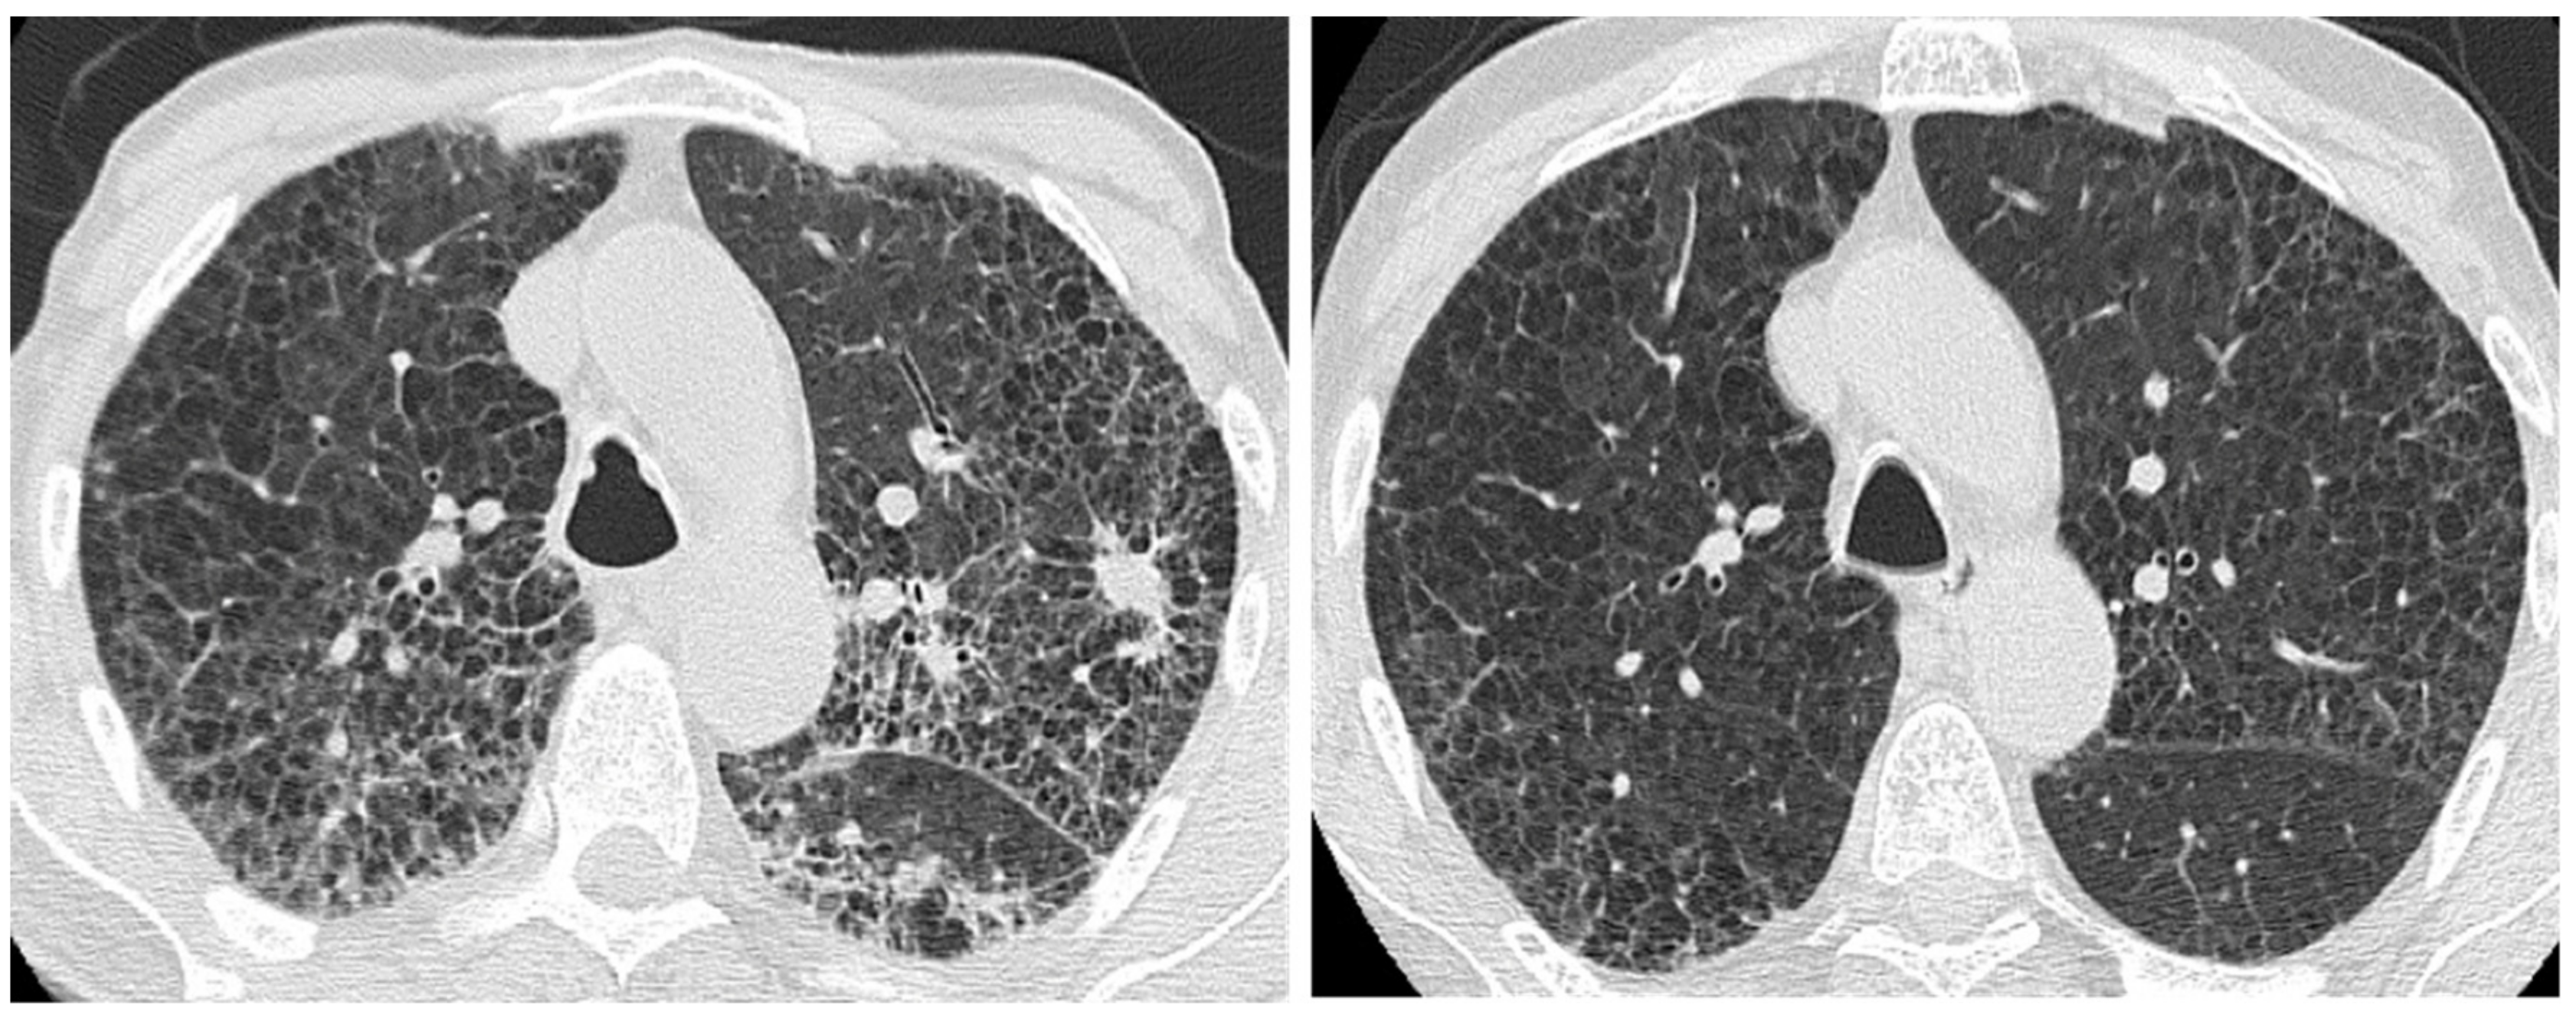

| Acute exacerbation IPF | New bilateral ground glass opacities and/or consolidation on a background of reticular or honeycombing pattern. | ||

| Right heart failure | Profuse septal thickening, ground glass opacities, pleural effusion on a background of reticular or honeycombing pattern. | ||